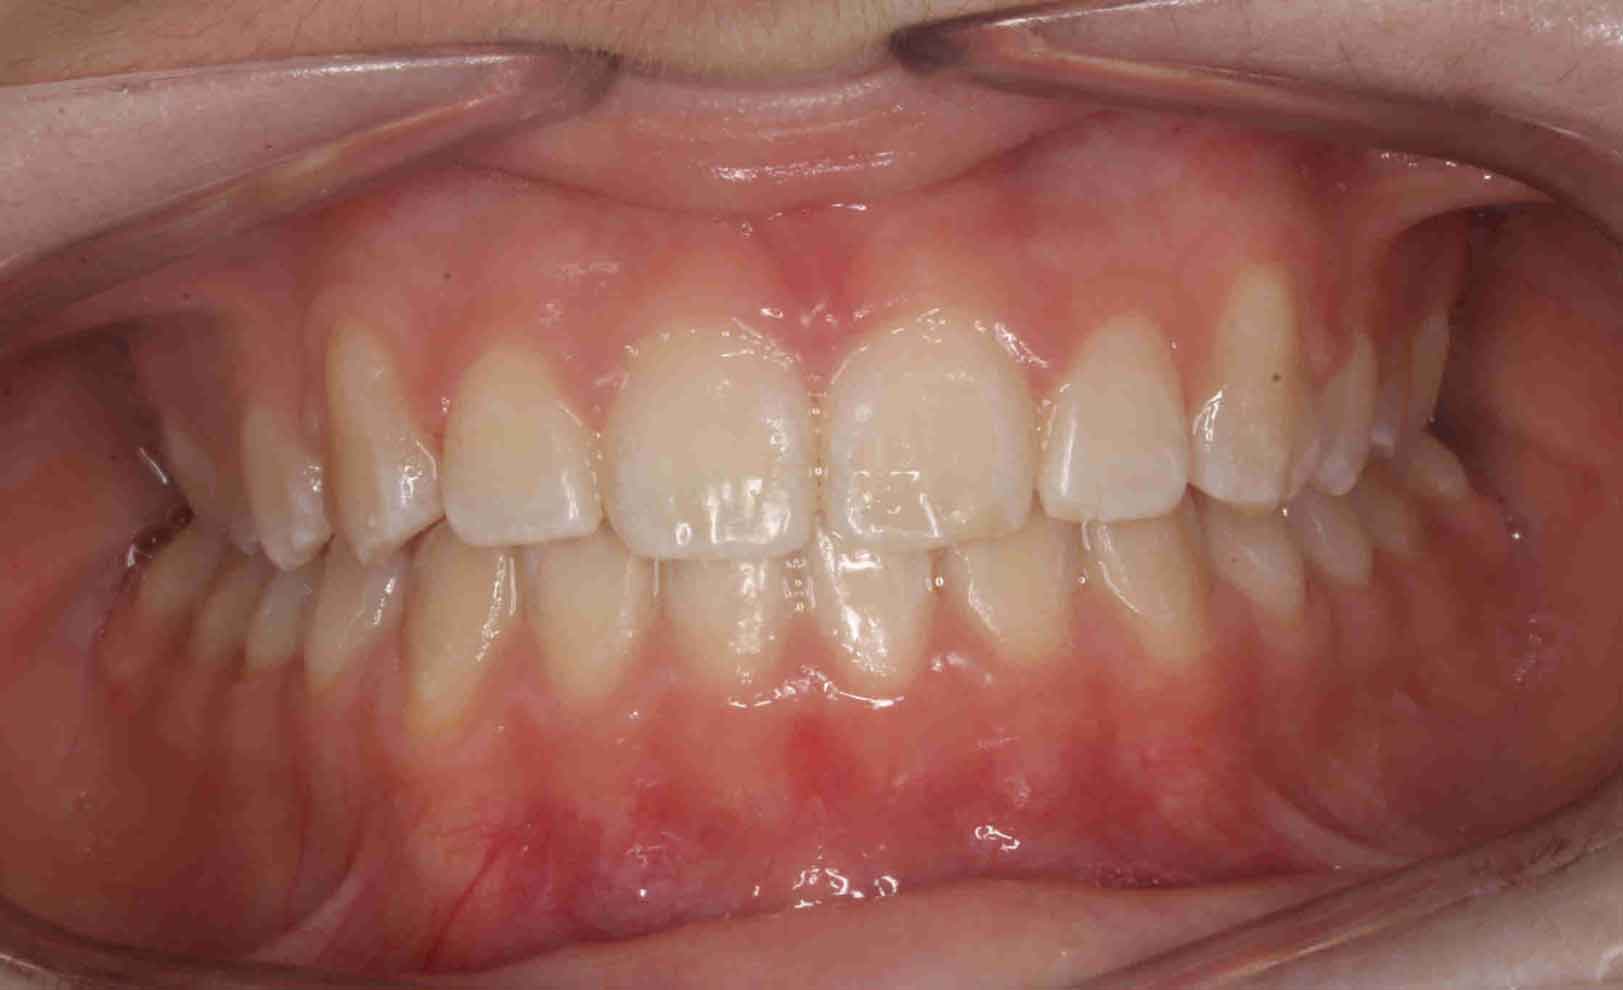

Caninos Impactados

En las siguientes imágenes puedes ver distintos resultados del tratamiento, deslizando la barra central de un lado a otro.